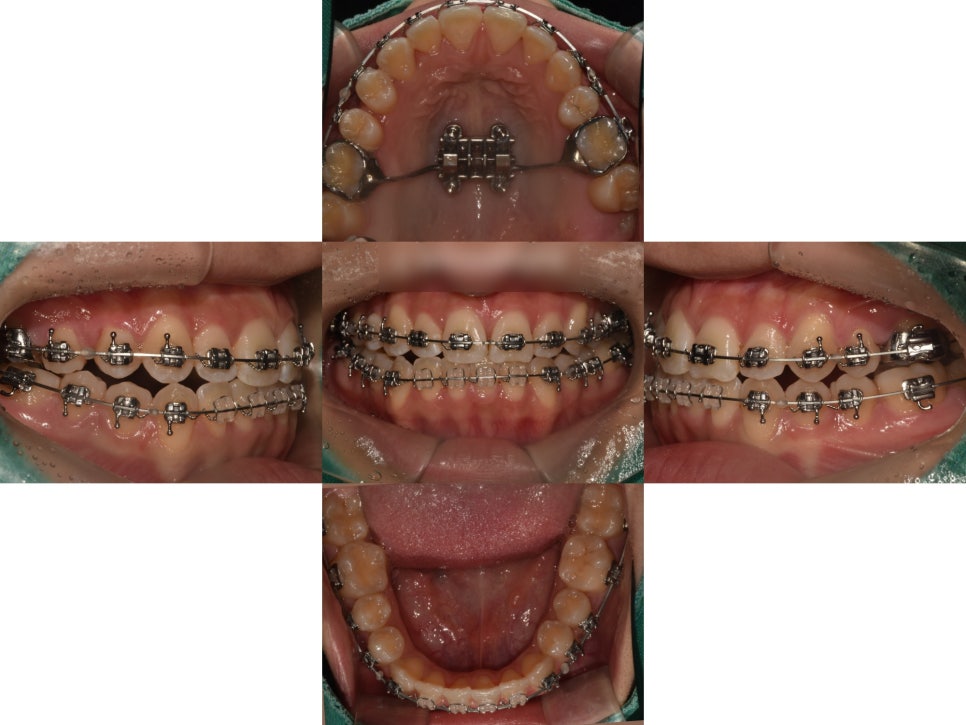

먼저, 윗니가 아랫니를 충분히 덮어줄 수 있도록

위턱을 확장시키는 작업을 진행했습니다.

(MARPE 장치 사용)

어느정도 위턱이 확장되면서

공간이 조금씩 생기기 시작할때,

치아들을 가지런하게 배열하며

오른쪽 결손부위로 인해 틀어진 정중선까지

최대한 일치시키는 이동계획을 잡았습니다.